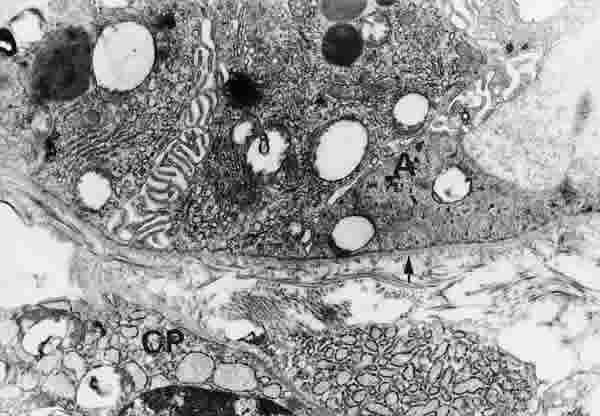

Figura 32

BIOPSIA EN UN PACIENTE CON SS1-GRADO I. LAS CÉLULAS ACINARES (A) TIENEN GRAN CANTIDAD DE ORGÁNULOS SUBCELULARES, AUNQUE CON ESCASOS GRÁNULOS DE SECRECIÓN EN POSICIÓN BASAL. LA MEMBRANA BASAS (FLECHA ARRIBA) ES MODERADAMENTE ANCHA Y CONTINUA. EN EL TEJIDO CONECTIVO SE OBSERVAN CÉLULAS PLASMÁTICAS (CP). MICROSCOPIA ELECTRÓNICA. MAGNIFICACIÓN ORIGINAL X6000.